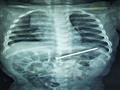

أعلن الدكتور أحمد الرفاعي، مدير مستشفى الأطفال بجامعة المنصورة، اليوم الخميس، إجراء فريق جراحى بوحدة الجهاز الهضمي عملية جراحية لاستخراج مسمار بطول 6 سم، باستخدام المنظار بدون أي جرح أو مضاعفات أو تدخل جراحى من بطن طفل عمره 9 شهور.

وذكر بيان لجامعة المنصورة، أن فريق طبي ضم الدكتور محمد عز الرجال، والدكتور أحمد مجاهد، استاذ طب الاطفال والجهاز الهضمي، والدكتور محمد مرسي، أخصائي اطفال وجهاز هضمى، والدكتور منصور صقر، أخصائي أطفال نجح فى استخراج المسمار دون جراحة.

وقال الدكتور محمد عز الرجال، أن الطفل كان يلهو مع شقيقه البالغ ٣سنوات فى عدم وجود الأم بعدها أخبرالطفل الكبير والدته أن أخيه ابتلع مسمار.

وأضاف:"الأم حاولت على مدار 6 أيام استخراج المسمار طبيًا، حتى جاءت مستشفى الاطفال وعرضت الحالة على الفريق الطبى لإجراء الاشعة لتحديد مكان المسمار.

واوضح عزالراجل أن العمليه انتهت بسلام دون مضاعفات وغادر الطفل المستشفى فى نفس اليوم.